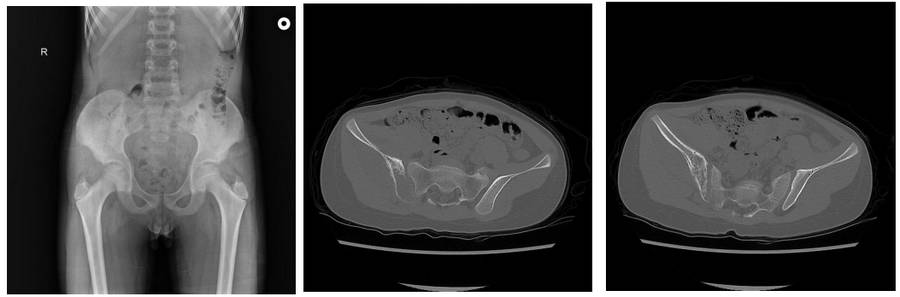

Ameliyat Öncesi: Röntgende sağ iliak kanatda düzensizlik, tomografide kemik harabiyeti ve periost reaksiyonu görülmekte